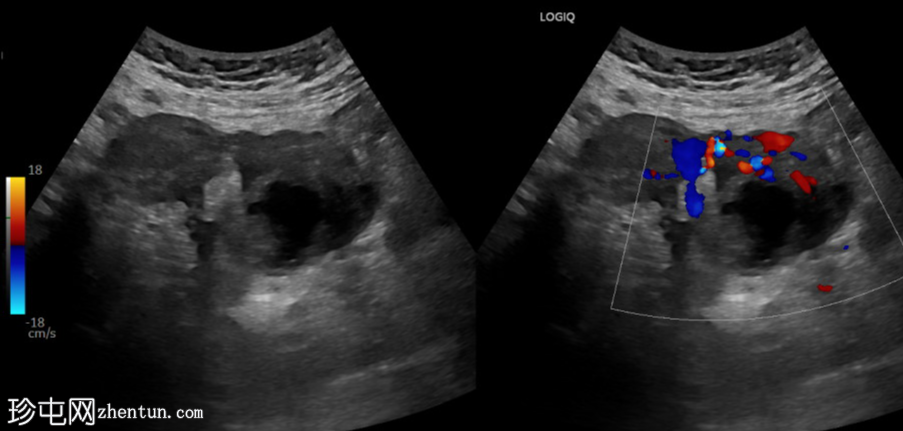

斜切面

左侧卵巢明显增大,可见一囊肿,大小约3.2 x 2.3 cm,呈火环征,可能为黄体囊肿。左侧卵巢与子宫之间可见一管状结构,直径约1.3 cm,内含浑浊液体,未见血管,最可能为输卵管积血。以上特征提示可能为左侧异位妊娠。

未见宫内妊娠囊。